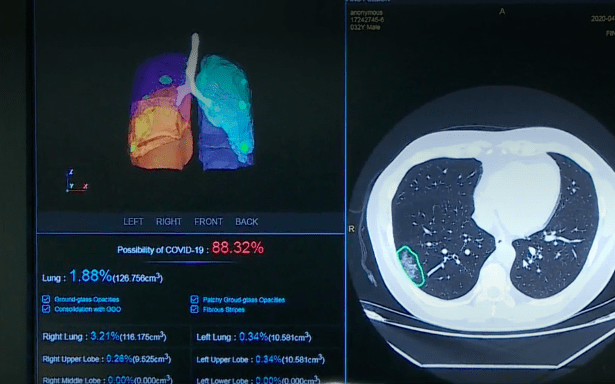

El funcionamiento de esta innovación se basa en los datos almacenados en la nube. Para esto, se le realiza un escáner de los pulmones al paciente sospechoso. Estos resultados serán comparados, a través de la inteligencia artificial, con más de 4.000 imágenes médicas de neumonía producida por Covid-19 en pacientes positivos. Además de contrastarlas con otras imágenes de casos negativos.

Una vez realizado eso, y en cosa de minutos, un algoritmo determinará el grado de similitud del caso sospechoso con los positivos, entregando un porcentaje de positividad del paciente al virus.

Junto con detectar casos positivos, y descartar los negativos, el sistema de Huawei permite realizar un «mapa» 3D de los pulmones del paciente. Acción que lleva a determinar el grado de daño de dicho órgano, lo que permitirá elegir la mejor forma de ventilación y verificación el grado de avance a medida que se realiza el tratamiento.